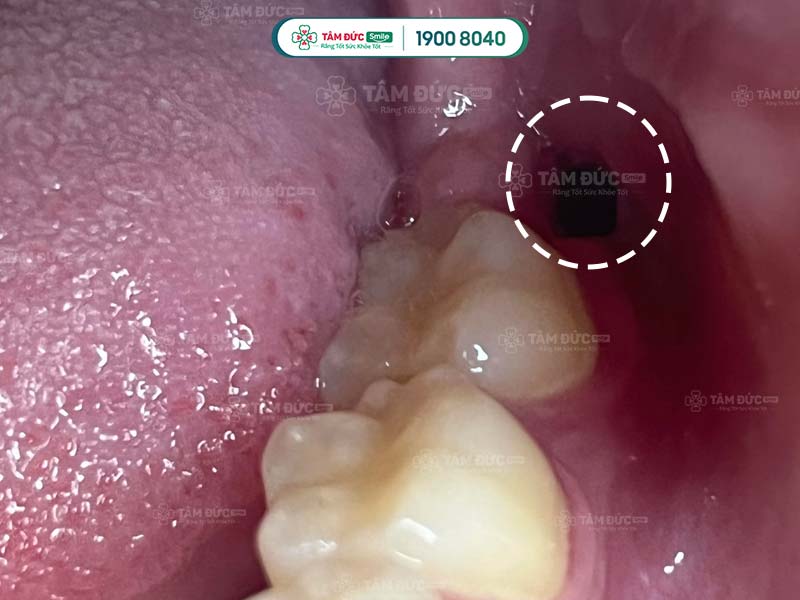

nhổ răng khôn 2 tuần vẫn đau do bị khô ổ răng

1.4. Khô ổ răng nên nhổ răng khôn 2 tuần vẫn đau

Khô ổ răng còn được biết đến là tình trạng viêm xương ổ răng, thường xảy ra sau khi nhổ răng khôn. Xác suất bị khô ổ răng chỉ chiếm chưa tới 2% trong số các biến chứng sau khi nhổ răng thường. Với nhổ răng khôn, tỷ lệ xuất hiện của biến chứng này có thể lên tới 20%.

Nguyên nhân gây khô ổ răng là do Quý khách không vệ sinh, chăm sóc răng miệng đúng cách. Điều này đã tạo điều kiện để vi khuẩn, hóa chất xâm nhập vào bên trong gây khô ổ răng. Quý khách có thể gặp phải tình trạng đau nhức kéo dài, cơn đau lan tỏa ra xung quanh, kèm theo đó là chứng hôi miệng.